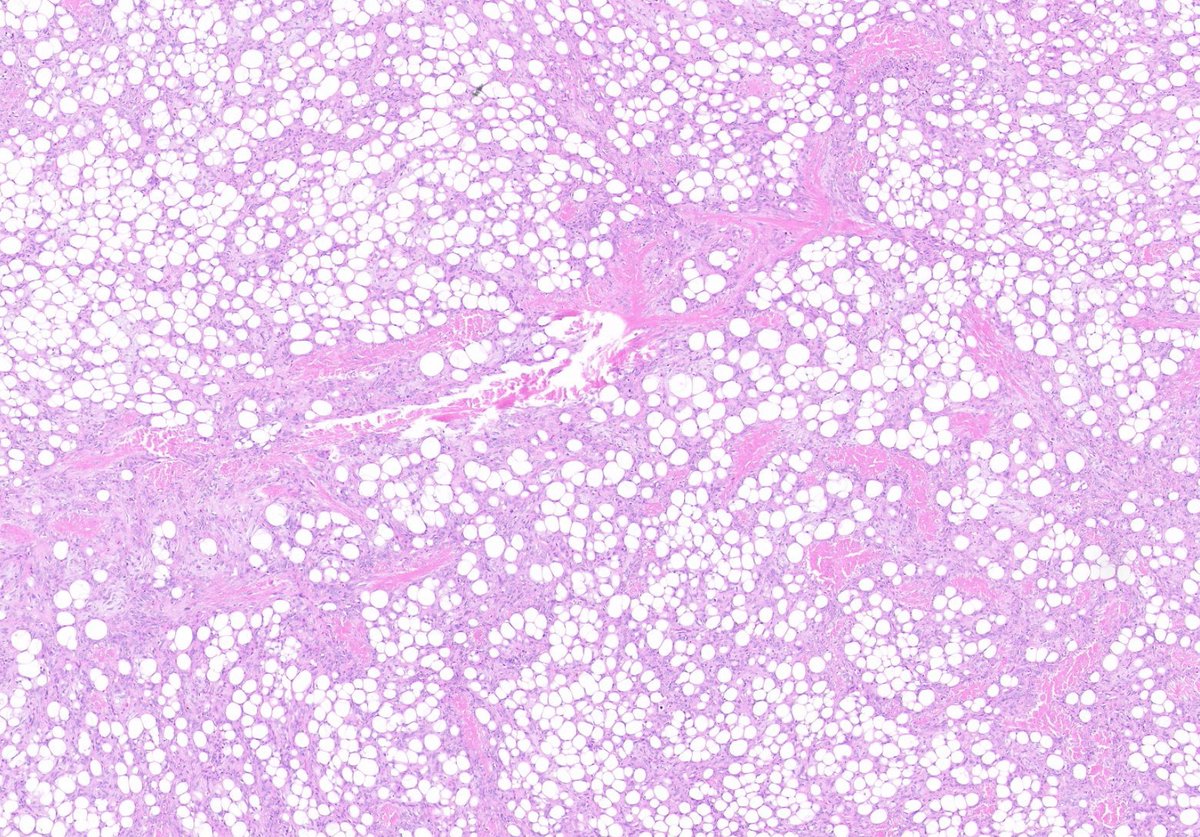

1. Organ 2. Dx?

11

14

49